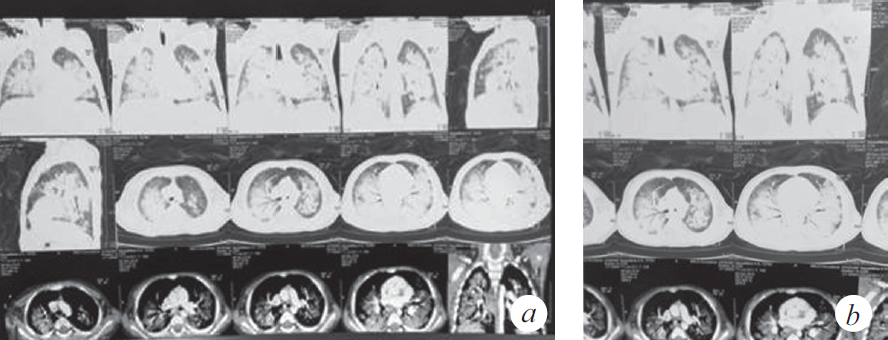

Продуктивный кашель с затрудненной эвакуацией мокроты впервые появился 12.12.2018, нарастала дыхательная недостаточность (одышка, кислородная зависимость), клинически и рентгенологически диагностирован спонтанный пневмоторакс справа (купирован дренированием). Во время дренирования развилась депрессия сердечной деятельности с переходом брадикардии в асистолию, с восстановлением ритма в течение 1 мин. после однократного введения адреналина и закрытого массажа сердца (15 с). Ребенок был переведен на искусственную вентиляцию легких (ИВЛ) (респиратор Savina, Dräger, Германия), отмечалась потребность в FiO2 0,6 для поддержания SpO2 92–95 %. Параметры вентиляции: SIMV, MV 6–7 мл/кг, PIP от 20 до 22 мбар; PEEP (режим BiPAP): минимум 4 мбар, максимум 8 мбар. На следующий день выполнена нижняя трахеотомия и установлена трахеостомическая канюля. Пациентка находилась на ИВЛ 2 мес. со стабильными показателями вентиляции, достигнутое снижение уровня респираторной поддержки было незначительным: PIP 16 мбар, FiO2 0,5, PEEP 4–6 мбар. Динамика газов венозной крови положительная: РО2 50–64 мм рт. ст., SvO2 74–82 %. Динамика КТ представлена на рис. 3–6. В целом томографические изображения характеризовались стабильностью, отличия связаны с эпизодами госпитальной пневмонии: зафиксировано 5 клинически ярких рецидивов. Конец второго месяца заболевания осложнился развитием диарейного синдрома клебсиеллезной этиологии, что заставило редуцировать объем питания на неделю. С декабря до марта отмечен отрицательный баланс по массе тела (минимальный показатель массы тела 8050 г).

Рис. 3. Компьютерная томография органов грудной клетки (через 8 нед. от дебюта заболевания) (a). Сохраняются КТ-признаки паренхиматозного поражения легочной ткани, отмечена положительная динамика в виде уменьшения плотности легочной консолидации (b)

Fig. 3. CT of the chest organs (8 weeks after the onset of the disease) (a). CT-signs of parenchymal lesion of the lung tissue are preserved, positive dynamics in the form of a decrease in the density of pulmonary consolidation are noted (b)

Рис. 4. Компьютерная томография органов грудной клетки (через 11 нед. от дебюта заболевания) (a). КТ-признаки преимущественно базального паренхиматозного поражения легочной ткани, появление выпота в правой плевральной полости (b)

Fig. 4. CT of the chest organs (11 weeks after the onset of the disease) (a). CT signs of a predominantly basal parenchymal lesion of the lung tissue, the appearance of effusion in the right pleural cavity (b)

Рис. 5. Компьютерная томография органов грудной клетки (через 4 мес. от дебюта заболевания) (a). КТ-признаки диффузного субтотального поражения легочной ткани с зонами консолидации в базальных отделах S2, S6, S10 справа и S6 слева, вероятно воспалительного характера (b)

Fig. 5. CT of the chest organs (4 months after the onset of the disease) (a). CT signs of diffuse subtotal lesion of the lung tissue with areas of consolidation in the basal sections S2, S6, S10 on the right and S6 on the left, probably of an inflammatory nature (b)

Рис. 6. Компьютерная томография органов грудной клетки (через 5 мес. от дебюта заболевания) (a). КТ-признаки интерстициального поражения легочной ткани с увеличением площади консолидации в медиальных отделах обоих легких с сохранением в базальных отделах S2, S6, S10 справа и S6 слева (b)

Fig. 6. CT of the chest organs (5 months after the onset of the disease) (a). CT signs of interstitial damage to the lung tissue with an increase in the area of consolidation in the medial sections of both lungs, while maintaining in the basal sections S2, S6, S10 on the right and S6 on the left (b)